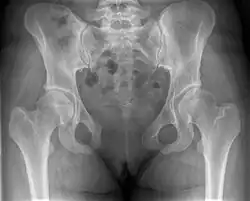

This abnormally wide gap can be diagnosed by radiologic studies such as X-ray, Ultrasound, MRI, CT scan or bone scan. While X-Ray is the gold standard to identify a separation of the pubic symphysis, a decision must be made in regard to which imaging modality to utilize that is patient and case-specific.[3]

X-ray

An X-ray film obtained in the AP view of the pelvic inlet and outlet will show a marked gap between the pubic bones.[3] A normal pelvis will show a gap that is 4–5 mm. However, in pregnancy the hormonal influences cause relaxation of the connecting ligaments and the bones separate up to 9 mm. A gap measuring greater than 10 mm indicates a pathological process.[3]

In addition, a view in the "flamingo stance" can be obtained to demonstrate the instability of the joint. This position consists of the patient standing with weight on one leg and the other bent.[6] A vertical displacement of more than 1 cm is an indicator of symphysis pubis instability.[7] A displacement of more than 2 cm usually indicates involvement of the sacroiliac joints.[3]

A limitation of this imaging study is that X-rays induce radiation and should be avoided during pregnancy.[3]